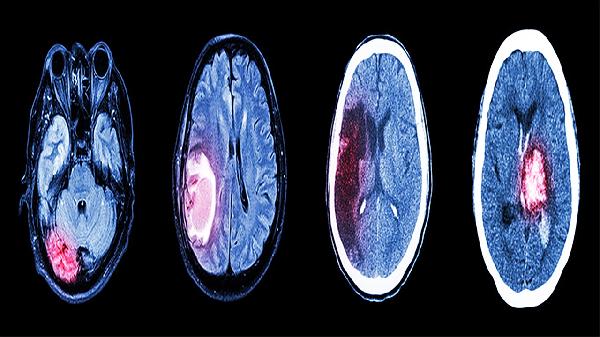

醒脑再造丸可用于治疗脑梗死恢复期及后遗症期。脑梗死可能与高血压、高脂血症、动脉粥样硬化等因素有关,通常表现为偏瘫、言语不清、头晕等症状。醒脑再造丸可通过扩张脑血管、改善脑部微循环帮助恢复神经功能,临床常与阿司匹林肠溶片、胞磷胆碱钠胶囊等药物联合使用。需注意急性期患者应在医生指导下规范使用溶栓或抗凝治疗。

醒脑再造丸适用于中风后遗留的神经系统功能障碍。中风后遗症可能与脑组织缺血缺氧损伤有关,常见半身不遂、口眼歪斜、反应迟钝等表现。该药能促进脑部侧支循环建立,可与脑蛋白水解物片、银杏叶片等药物协同治疗。日常需配合康复训练以增强疗效。

醒脑再造丸对脑动脉硬化导致的慢性脑供血不足具有改善作用。脑动脉硬化通常与血脂异常、糖尿病等因素相关,患者可能出现头痛、记忆力减退、睡眠障碍等症状。该药能抑制血小板聚集,减轻血管内皮损伤,临床常联合瑞舒伐他汀钙片、尼莫地平片等药物控制病情进展。

醒脑再造丸对脑血管病变引发的认知功能下降有一定疗效。血管性痴呆可能与多发性脑梗死、皮质下动脉硬化性脑病有关,表现为定向力障碍、计算力减退等。该药通过改善脑代谢发挥作用,可与盐酸多奈哌齐片、奥拉西坦胶囊等药物联合使用。建议患者进行认知功能训练。